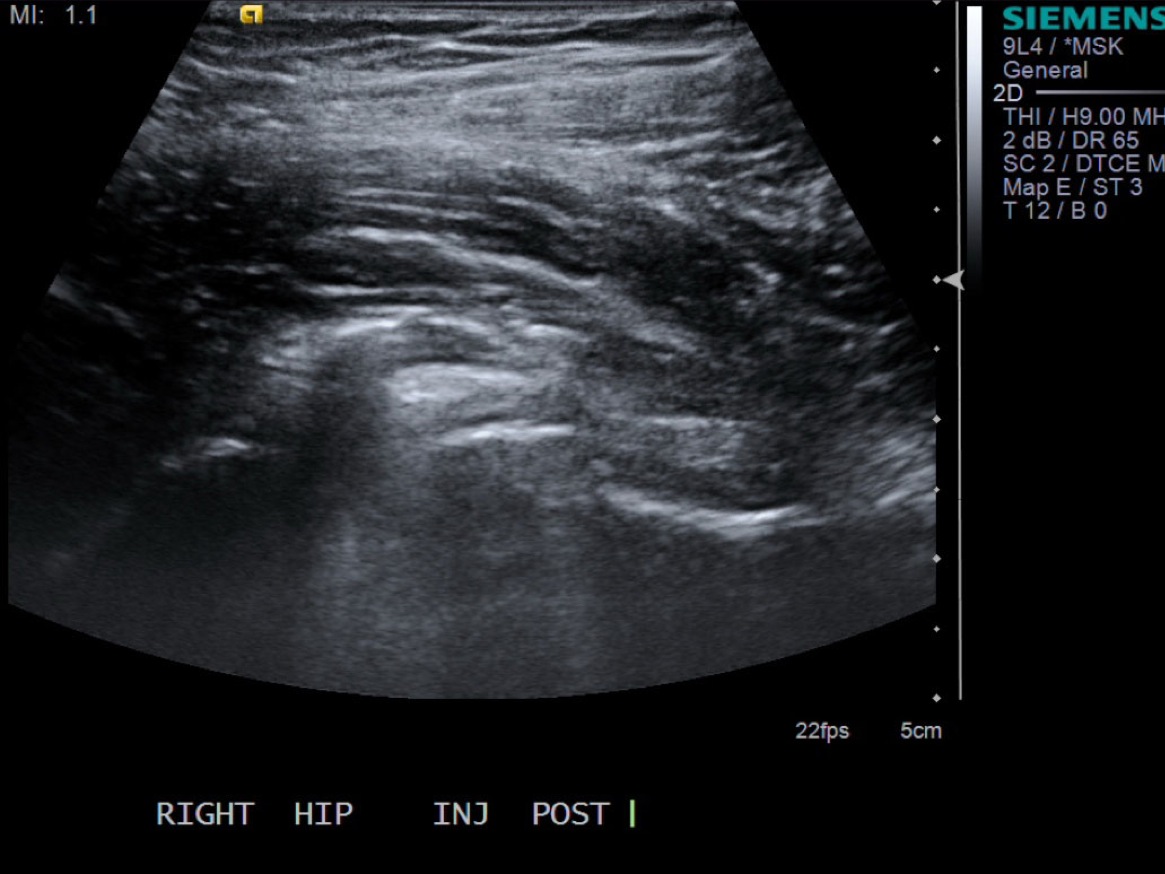

10. Test inject to see if easy flow with 1% lidocaine. If no resistance and see distention of the tendon sheath, exchange for 5cc syringe with injectable steroid and ropivacaine.

12. Scan joint to demonstrate distention. Can try to flex hip to see if fluid distended.

• descriptiondescription